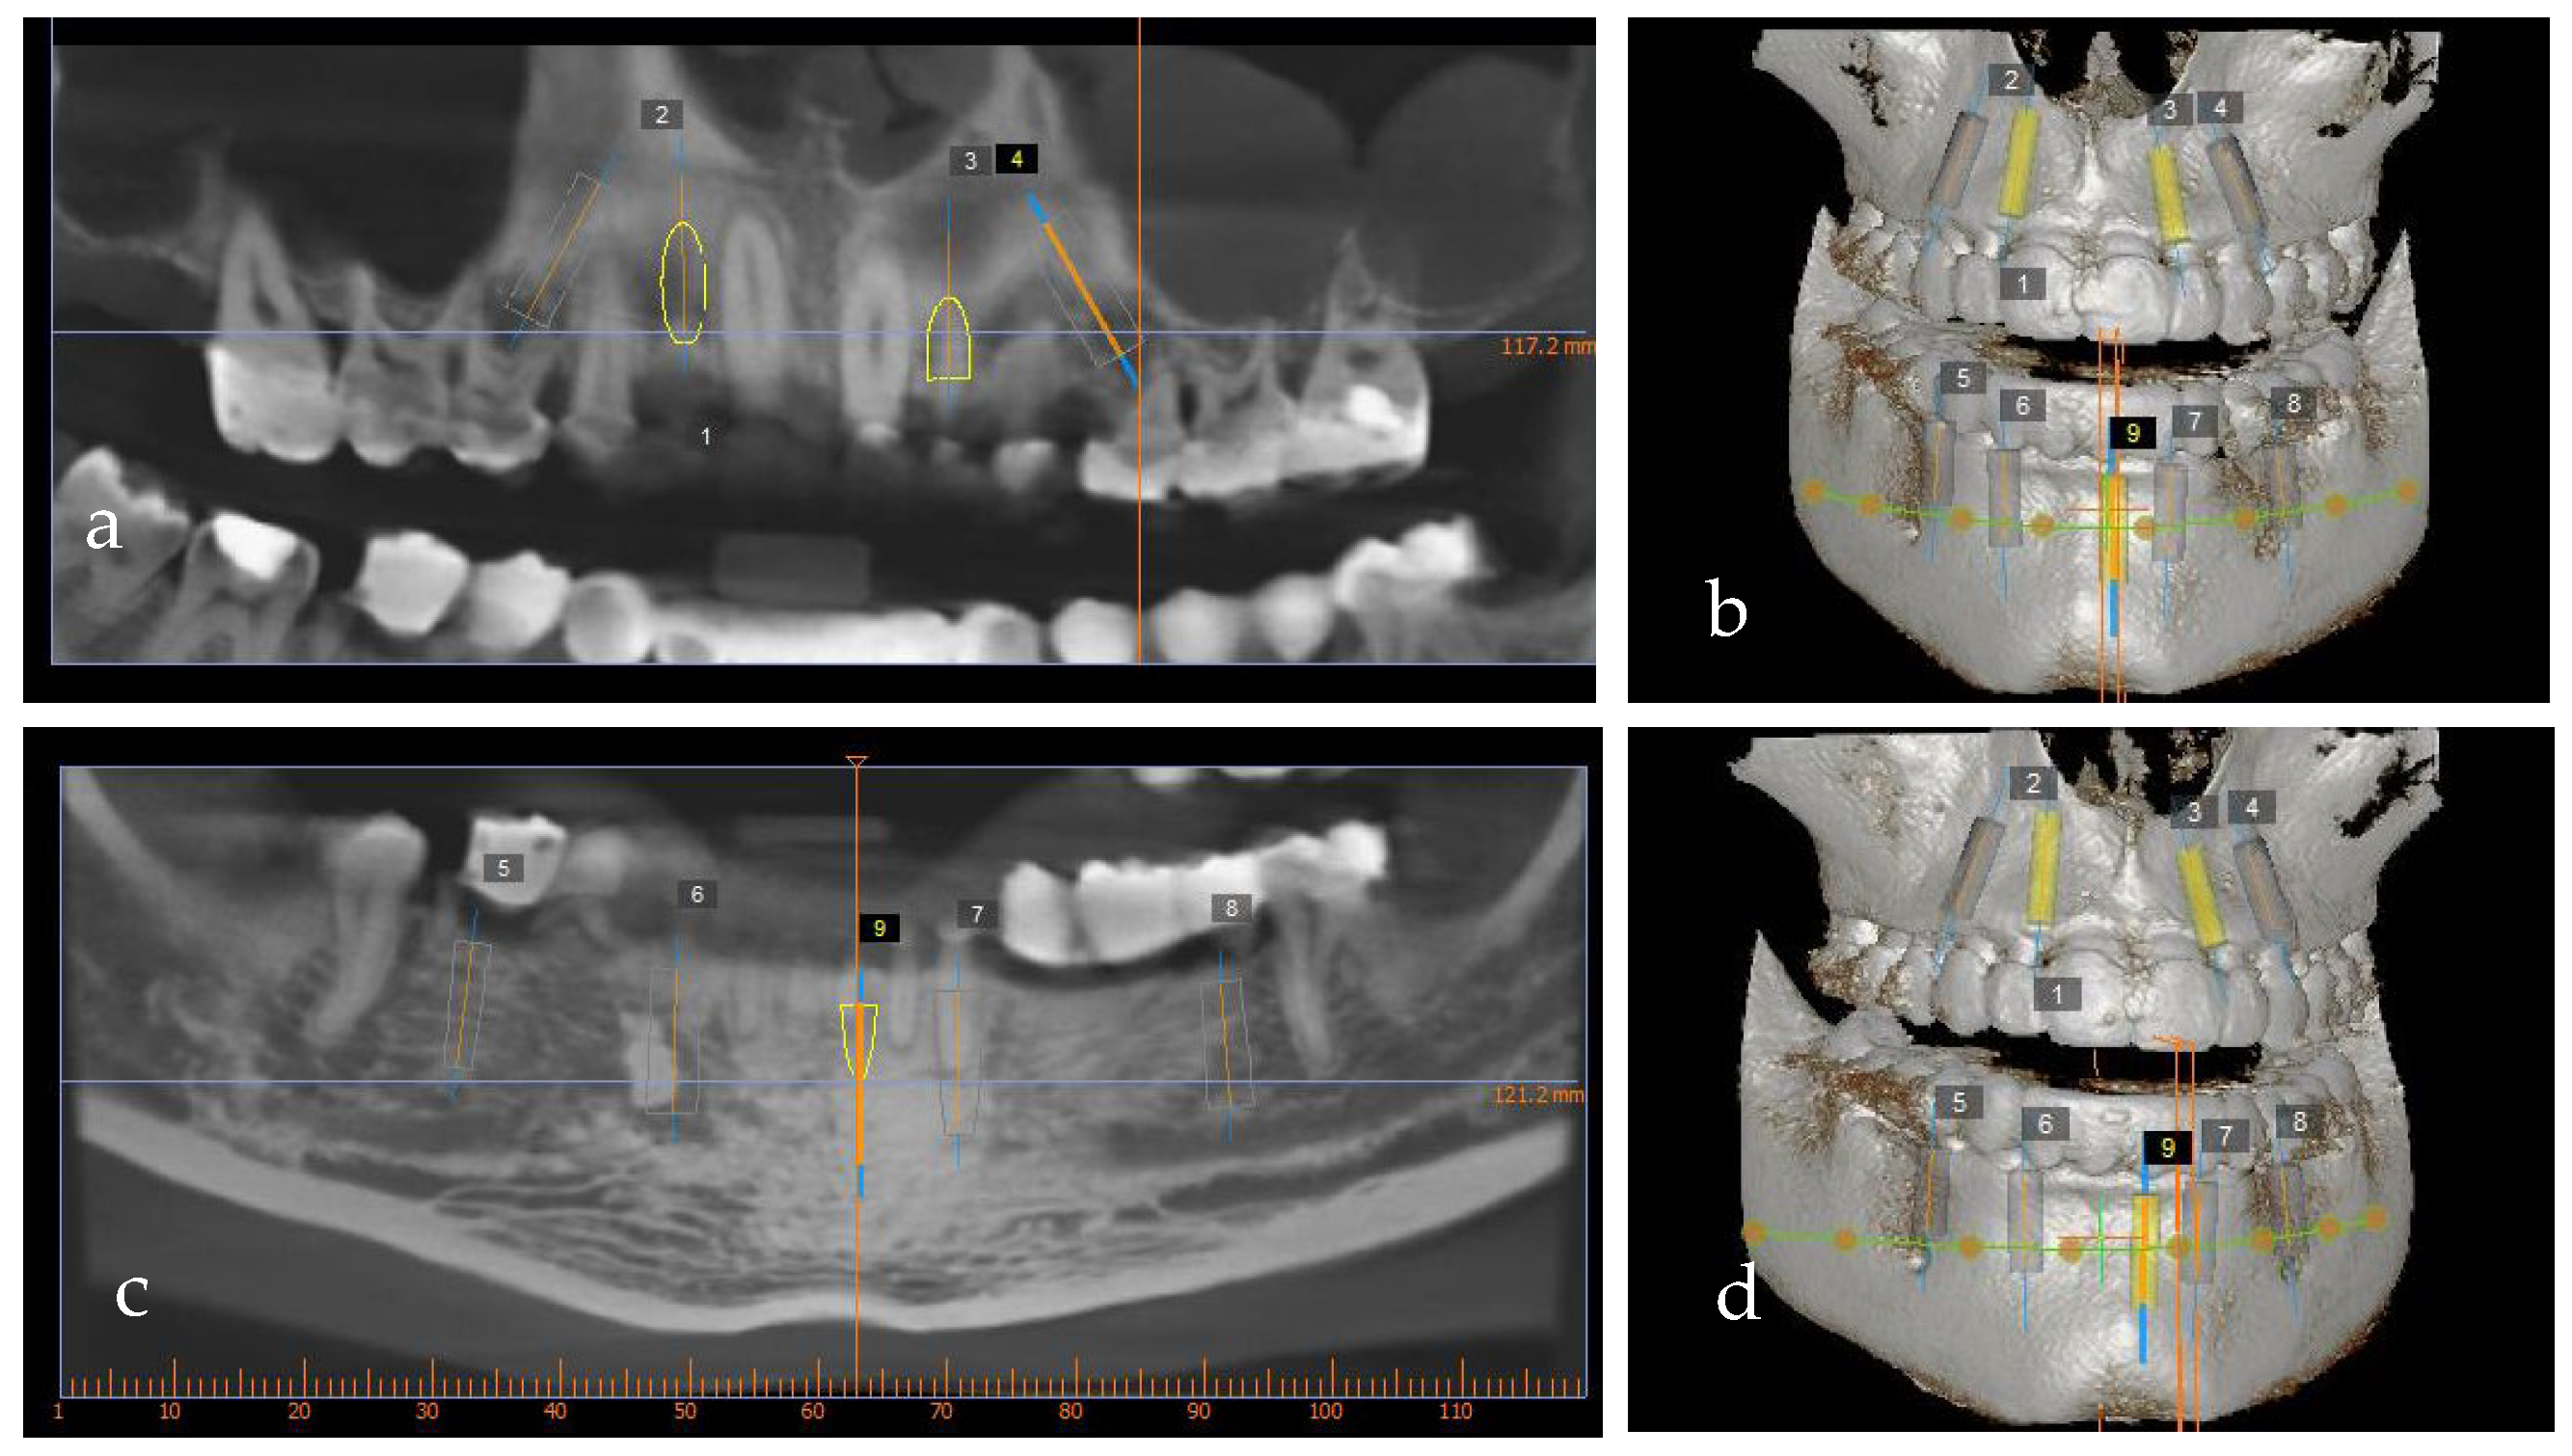

Figure 8.

Implant planning software using cone-beam computerized tomography: (a,b) maxilla and (c,d) mandible.

The wax-up also served as a prosthetic guide for the implant position. To precisely plan the implants’ placement from a prosthetic point of view, a CBCT (PaxFlex 3D, Vatech, Hwaseong-si, Republic of Korea) was performed and an initial digital planning software analysis was conducted with Easy3DPlus version 1.2 (Vatech, Hwaseong-si, Republic of Korea) (Figure 8a–d). Based on the previsualized implant placement, surgical guides were designed (Figure 9a,b), to achieve exact implant placement. The guides were designed in the Blue Sky Plan® software version 4.9.4 (Libertyville, IL, USA) and the surgical templates were fabricated using Dental SG resin (Formlabs, Somerville, MA,USA).

Using digital planning, the placement of nine implants, four on the maxilla and five on the mandible, was established (Figure 8a–d) based on the position of the provisional restorations. The implants were planned to be placed in the optimal prosthodontic position; tooth size, bone quality and volume, and the location of the mandibular nerve and sinus were also taken into consideration.